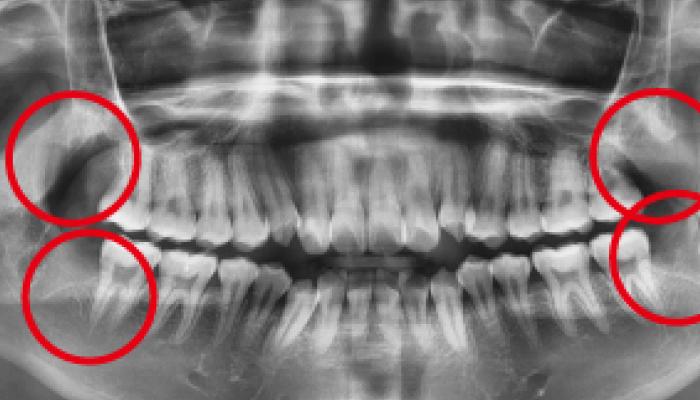

사랑니가 신경과 맞닿아 있는 상황을 제외하고는 안전하고 신속하게 발치가 가능합니다. 사랑니가 비스듬하게 누워있는 경우에는 수술적인 방법을 통해 발치를 해야합니다.

사람에 따라 다르지만 사랑니는 대부분 뼈의 자리가 부족하거나 기울어져 나거나 일부분에만 나오게 되어 관리가 매우 힘들고 인접 치아에 충치까지 유발할 수 있습니다. 매복사랑니는 고난이도 기술이기 떄문에 숙련된 의사의 발치가 중요합니다.

사랑니 발치 전후 사례

• 치료 전

치료 후